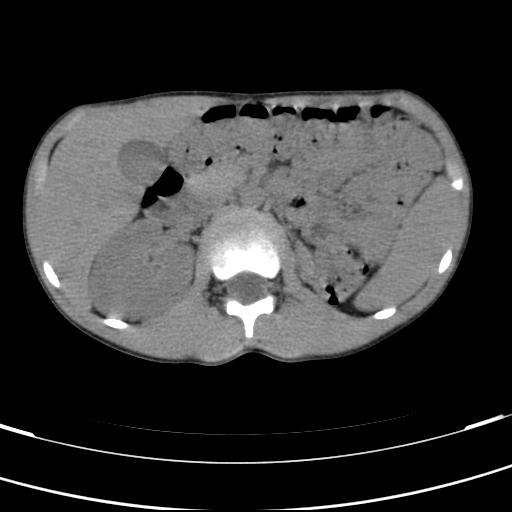

标题: PED3157:左肾缺如,请教脾脏的改变?、、

男孩,9岁。胃部不适。

脾脏位于左侧,但数个脾脏呈分离状态,左肾缺如,右肾代偿肥大。考虑多脾综合征。

脾脏变异,左肾未见,游走、异位、发育不全都要可能,增强或ivp造影。